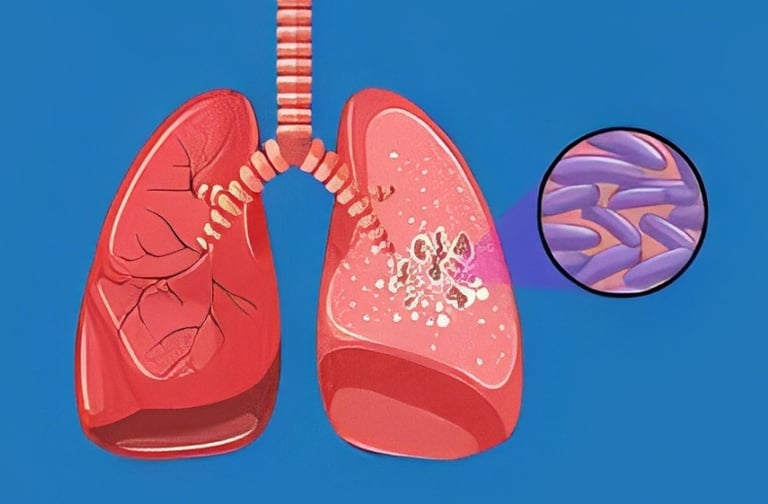

X-rays are also essential tools for diagnosing and managing diseases that affect the lungs, such as pneumonia, tuberculosis, and chronic obstructive pulmonary disease (COPD).

Chest x-rays are a primary tool for doctors when diagnosing respiratory conditions. A chest x-ray can show signs of pneumonia, detect lung infections, and reveal the extent of damage caused by conditions like emphysema and COPD. It can also be used to identify pleural effusions, which are abnormal fluid buildups around the lungs that can occur in diseases like tuberculosis or cancer.

Early Detection of Tuberculosis (TB)

In countries with high rates of tuberculosis, chest x-rays are crucial in identifying the disease in its early stages. TB can cause significant damage to the lungs, and detecting it early allows for more effective treatment. In fact, many international health organizations rely on x-ray technology to screen for tuberculosis in populations at risk.